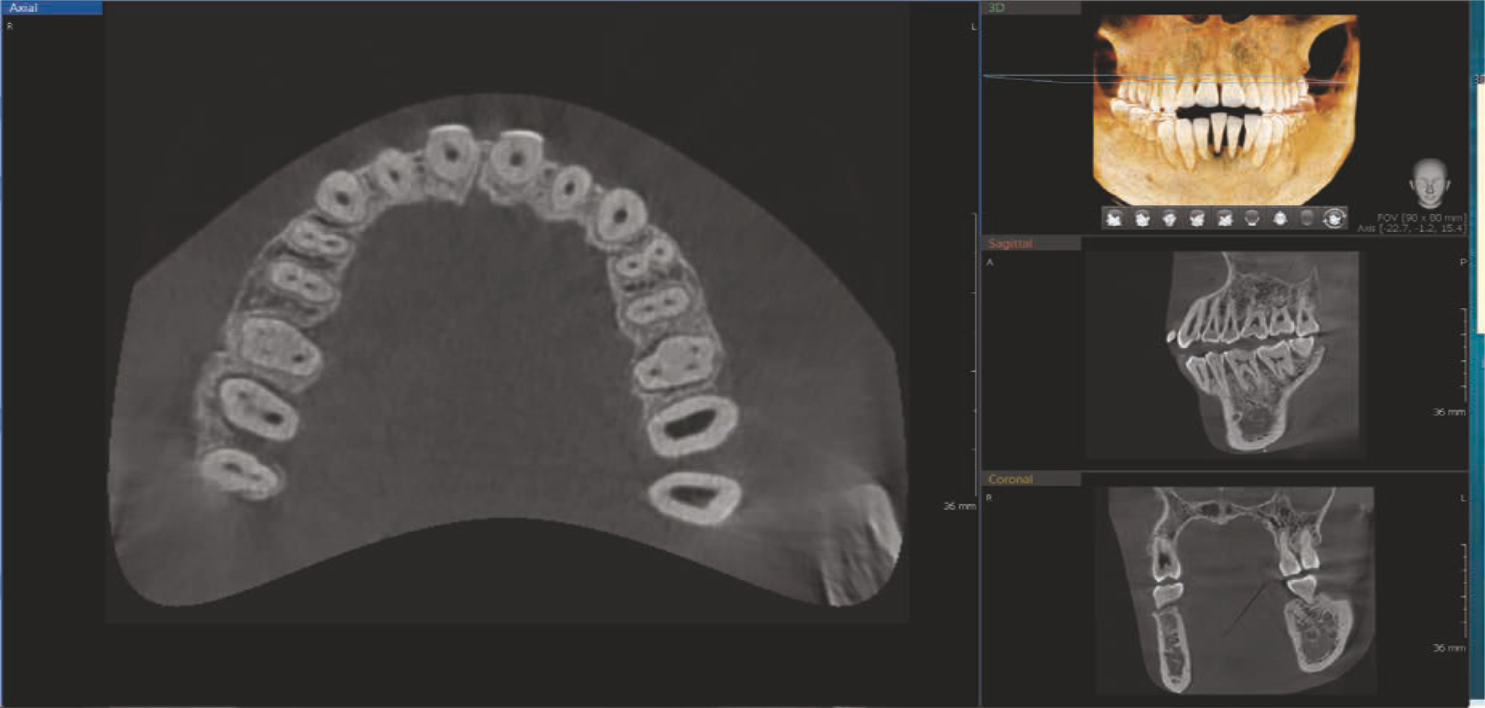

8X8 images enable fundamental diagnosis and treatment planning, including both the maxillary & mandibular areas, in a single scan. It is useful for complex implant surgeries.